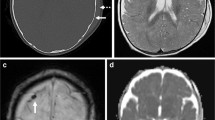

Rooks et al. reported SDH in 46 % of asymptomatic newborns MR within 3 days of birth, with lowest rates reported with caesarian section and the highest rates reported in assisted vaginal deliveries [134]. Lower rates of detection have been reported in other studies with decreased field strength [135] and longer time to initial imaging [136]. Birth-related SDH in these studies were generally dependent and thin (< 3 mm) (Fig. 12). All resolved within the first postnatal month [134, 136]. Evolution to chronic SDH was not demonstrated, as expected given lack of predisposing factors [62•]. One patient in the study by Rooks et al. had a new separate SDH incidentally noted on a 2-week follow-up examination in the context of benign enlargement of the subarachnoid space, which subsequently resolved by 3 months.

Non-Traumatic SDH

SDH is reported to occur in the context of numerous underlying medical conditions, though these are rare. Potential etiologies include vascular malformations, hematologic malignancies, coagulopathy (Fig. 2), and metabolic disorders such as Menkes kinky hair syndrome and glutaric aciduria type I (Fig. 13). Awareness of underlying medical conditions that might present with spontaneous hemorrhage that can mimic AHT is crucial for accurate diagnosis, and reinforces the notion that the evaluation of AHT must be accomplished in a multi-disciplinary fashion on a case-by-case basis.

6-month-old male with developmental delay and macrocephaly, subsequently confirmed to have glutaric aciduria type I. Axial T2-weighted image shows bilaterally enlarged perisylvian subarachnoid spaces secondary to frontal and temporal opercular hypoplasia and a left subdural collection (black arrows)

Benign Enlargement of the Subarachnoid Space (BESS)

From 0.5 to 0.8 in 1000, children will demonstrate mild to moderate enlargement of the subarachnoid spaces in the first 18 months of life, resulting in macrocephaly [139]. This appearance can easily be confused with hypodense bifrontal SDHs, particularly on CT. A key discriminating feature is the presence of normal subarachnoid vessels traversing the enlarged fluid space in BESS; these vessels are notably absent in SDH, in which case the subarachnoid space is compressed over the cerebral convexities (Fig. 14). Slight differences in signal intensity between the different fluid spaces is often accentuated on the FLAIR sequence, and the displaced dural-arachnoid membrane can be well visualized on high-resolution steady-state free precession sequences (CISS, FIESTA, and b-FFE) in unclear cases.